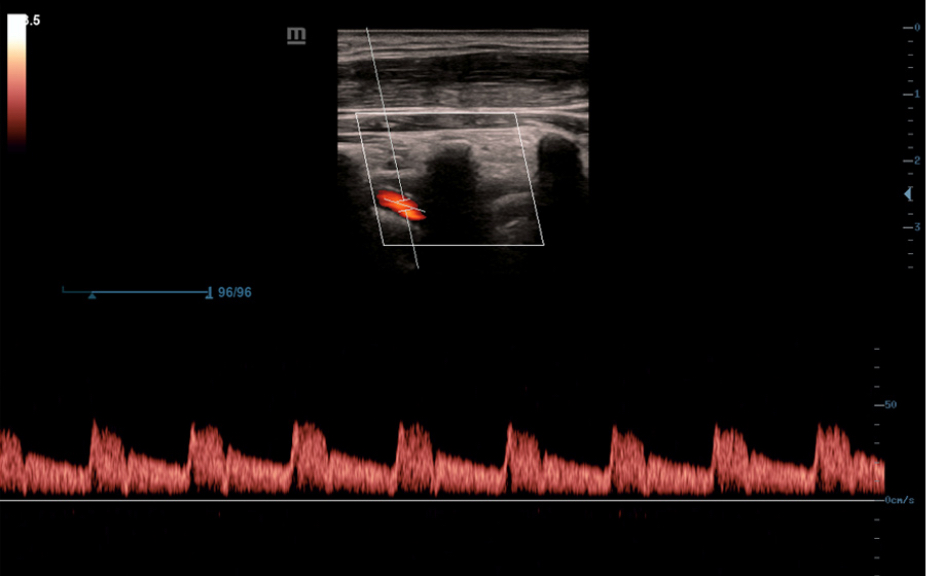

?ematik ve ultrason resimleri dahil, normal anatomik g?sterimler.

Standart ultrasonogram?n, ilgilenilen b?lge ĂŒzerinde g?rsel rehberlik sa?layan yan

g?rĂŒnĂŒmĂŒ.

Standart ultrason g?rĂŒntĂŒleri

3

Referans i?in ger?ek zamanl? tarama kar??la?t?rmas?.